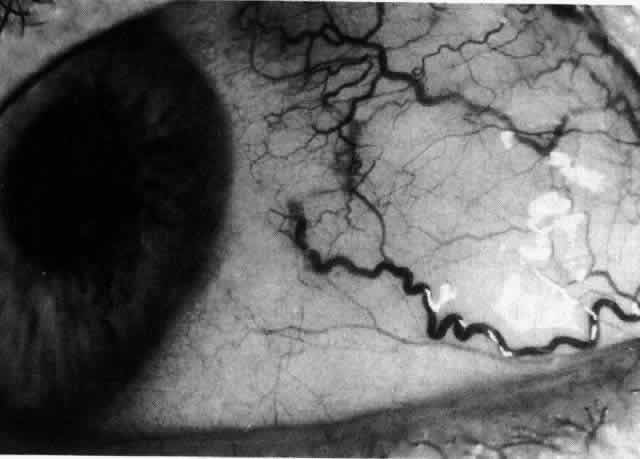

The characteristic features of necrotizing scleritis on fluorescein angiography are hypoperfusion and, eventually, nonperfusion of the vascular networks (Figs. 40 through 43).26 The initial changes are on the venous side of the capillary network; the transit time of the dye increases even if the eye is red and congested. If the disease process persists or has been present for a long time, thrombosis and permanent vaso-occlusive changes occur. These vessels (or the occluded capillary network) are bypassed by the opening of anastomotic channels. New vessels in a granuloma give rise to deep intrascleral leakage of dye (see Fig. 43). Conjunctival and episcleral involvement by the destructive change is late but is always preceded by vaso-occlusive changes that can sometimes be detected with use of the red-free light on the slit lamp (Figs. 44 and 45).

Fig. 40. Early necrotizing scleritis. There is characteristic yellow discoloration of the sclera underlying the conjunctiva at a point of necrosis. In this instance a small filament of tissue has penetrated the conjunctiva.

Fig. 41. Late stage of fluorescein angiogram adjacent to the site of necrosis in the same patient as in Figure 40. Although the eye is uniformly congested, the area near the necrosis shows vascular shutdown, whereas the rest of the conjunctiva and episclera is normally perfused.